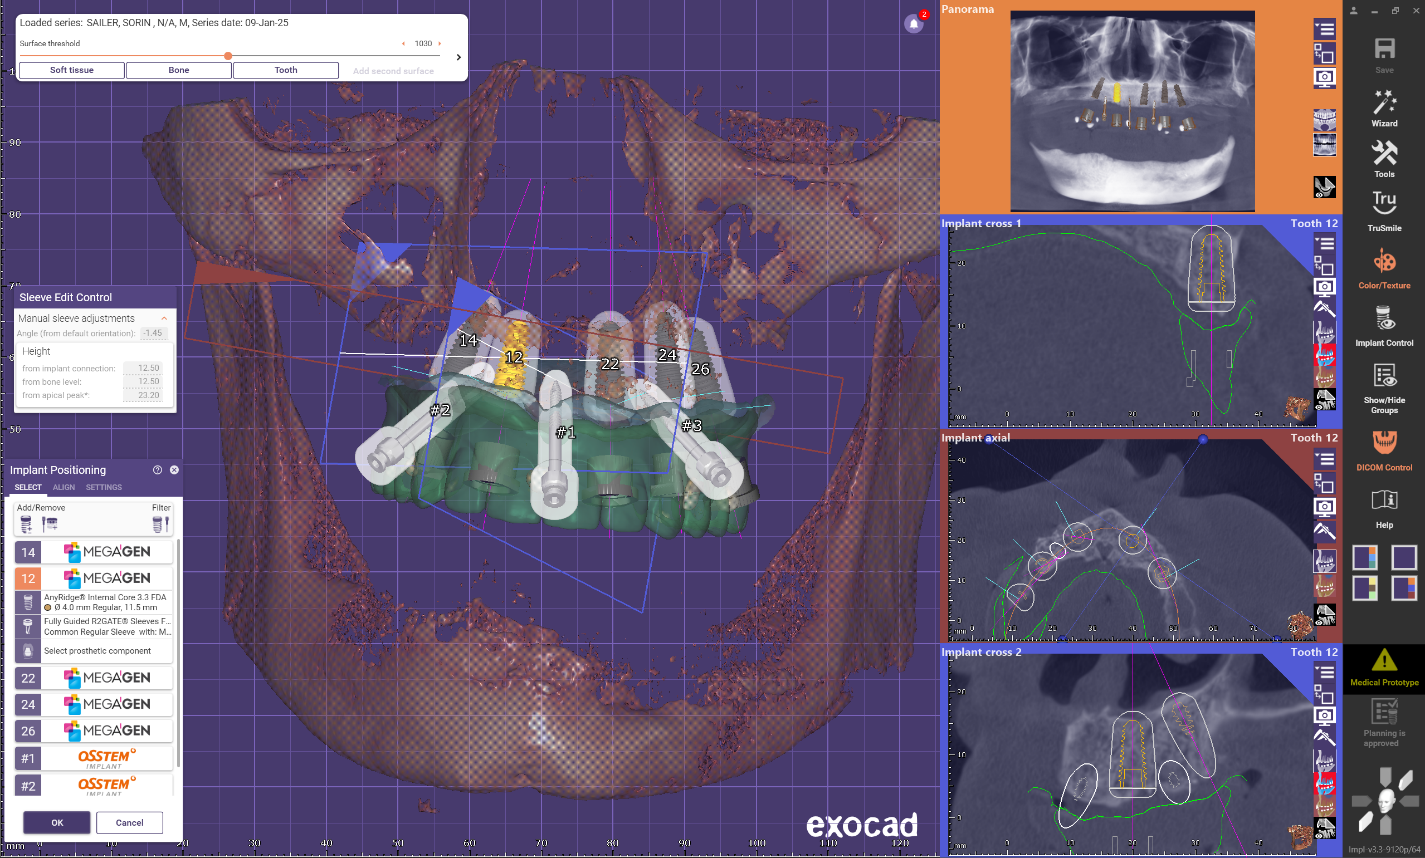

Implant placement planning done in EXOPLAN involved careful digital matching of the CBCT, wax-up, and facial scan data, resulting in an accurate, digitally-produced try-in prosthesis (Fig. 8). The validated prosthetic design was subsequently integrated with the software to plan placement of five strategically positioned implants in the upper arch.

A modified full arch guide was produced that allowed for implant placement with a flapped approach and no tissue punching for preservation of fixed soft tissue and visual verification of maxillary bone.

Guides produced in Exoplan . Irrigation is easily achievable and soft tissue can be repositioned to not get harmed by the burr .